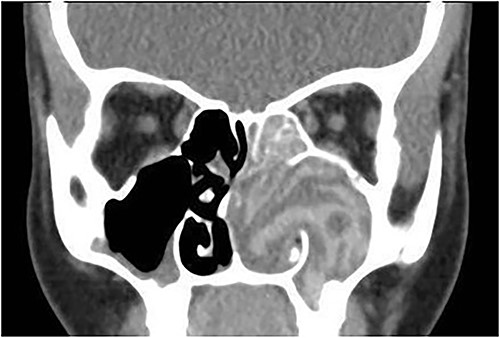

A 12-year-old female presented with unilateral left-sided nasal discharge and progressive nasal obstruction. Computed tomography (CT) scan of the paranasal sinuses (Fig. 1) confirmed the diagnosis of AFS. Functional Endoscopic Sinus Surgery (FESS) was performed to clean the sinuses from polyps, mucin and fungal debris, foll owed by medical treatment. The patient remained symptom-free for 3 years follow-up.

Coronal CT paranasal sinuses shows unilateral heterogeneous opacity of the obliterated left maxillary and ethmoid sinuses with extension through the widened remodeled ostiomeatal complex obliterating the left nasal cavity.